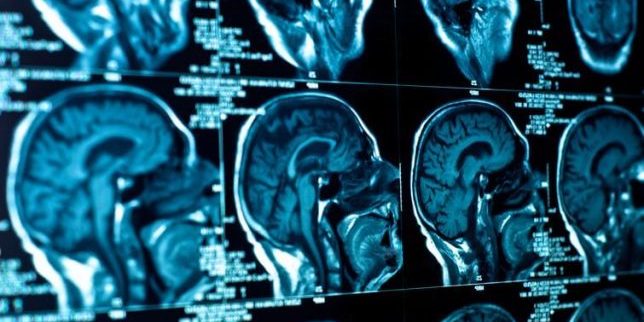

После COVID-19 могут возникать симптомы нарушений в работе мозга

Ученый назвал в интервью симптомы, которые могут возникать после перенесенного коронавируса. Их появление – сигнал нарушений, произошедших в работе головного мозга, заметил эксперт. Об этом он рассказал, объясняя, по каким проявлениям можно определить спровоцированные COVID-19 нарушения психики.